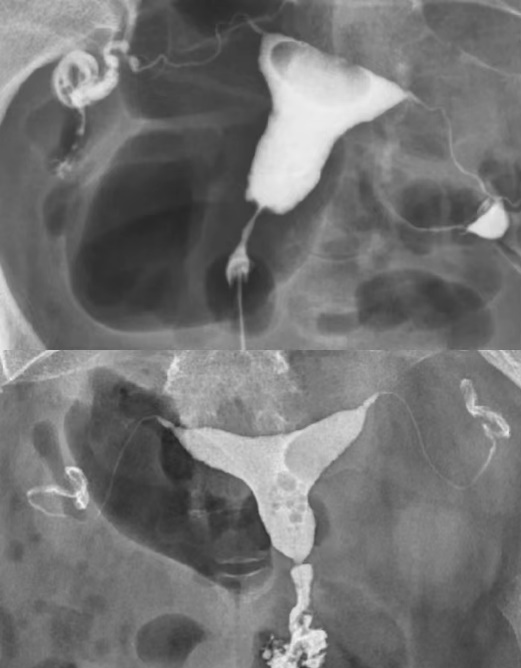

(一)食道钡剂造影

(二)胃全景、胃小沟与胃小区局部放大精细数字图像